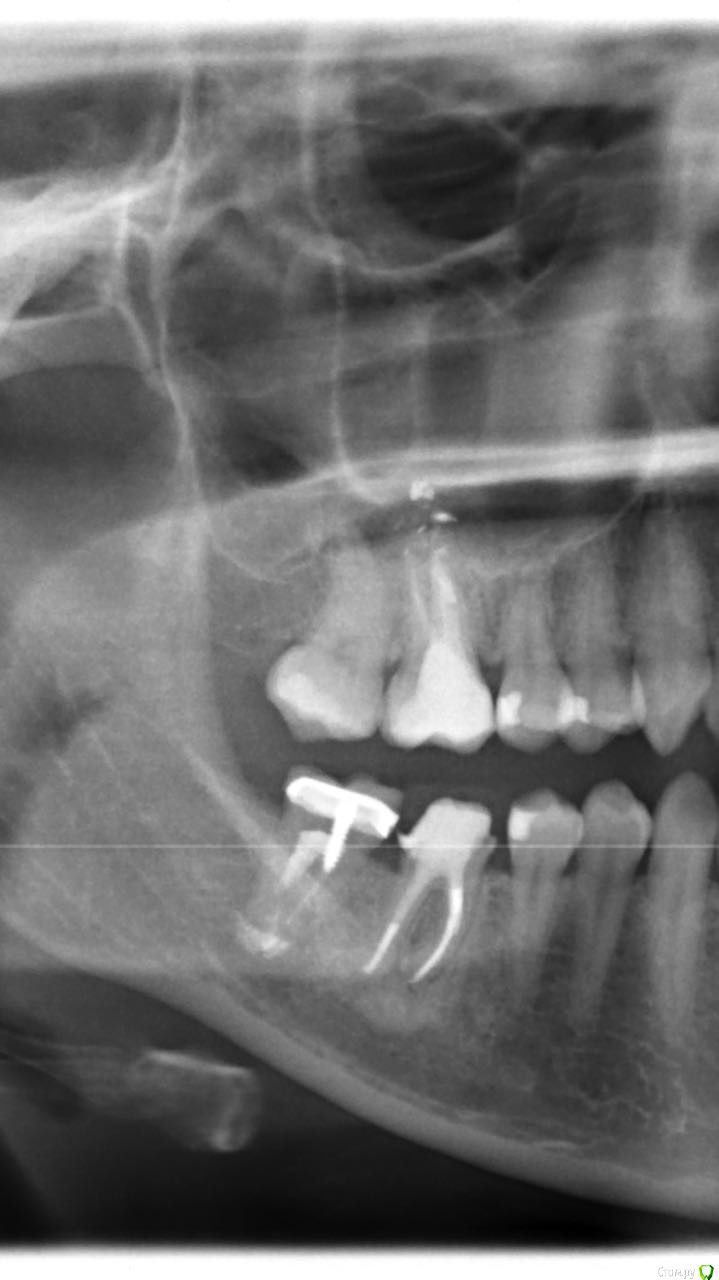

amys Опубликовано 1 августа, 2017 Поделиться Опубликовано 1 августа, 2017 Здравствуйте!Два дня назад 7й нижний зуб справа обломился под самый корень вместе со штифтом и коронкой. Каналы лечились 25 лет назад, возможно, резорцин-формалиновым способом (когда я ставила на него коронку, ортопед сказал, что в корни лучше не лезть). На приеме терапевт сказал, что зуб придётся удалять, так как при постановке вкладки корень может треснуть, но на всякий случай, посоветовала консультацию ортопеда. Ортопед сказал, что возьмётся сделать вкладку на имеющихся каналах, так как перелечить их вряд ли получится. Вопрос: имеет ли смысл ставить вкладку в данной ситуации, или стоит попытаться перелечить каналы? Если каналы были лечены резорцин-формалином, возможно ли их вообще перелечить? Спасибо. Ссылка на комментарий

amys Опубликовано 2 августа, 2017 Автор Поделиться Опубликовано 2 августа, 2017 Это снимок ДО того, как зуб отломился. А почему не попробовать полечить? Или в процессе лечения могут возникнуть осложнения? Ссылка на комментарий